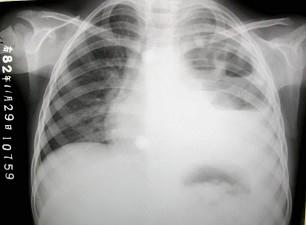

女,8岁,寒战、高热一周,如图所示,最可能的诊断为?(?)A.左侧肺不张B.左侧胸腔积液C.左侧多发性肺脓肿D.左心室增大E.以上都不正确

选项 A.左侧肺不张 B.左侧胸腔积液 C.左侧多发性肺脓肿 D.左心室增大 E.以上都不正确

答案 C